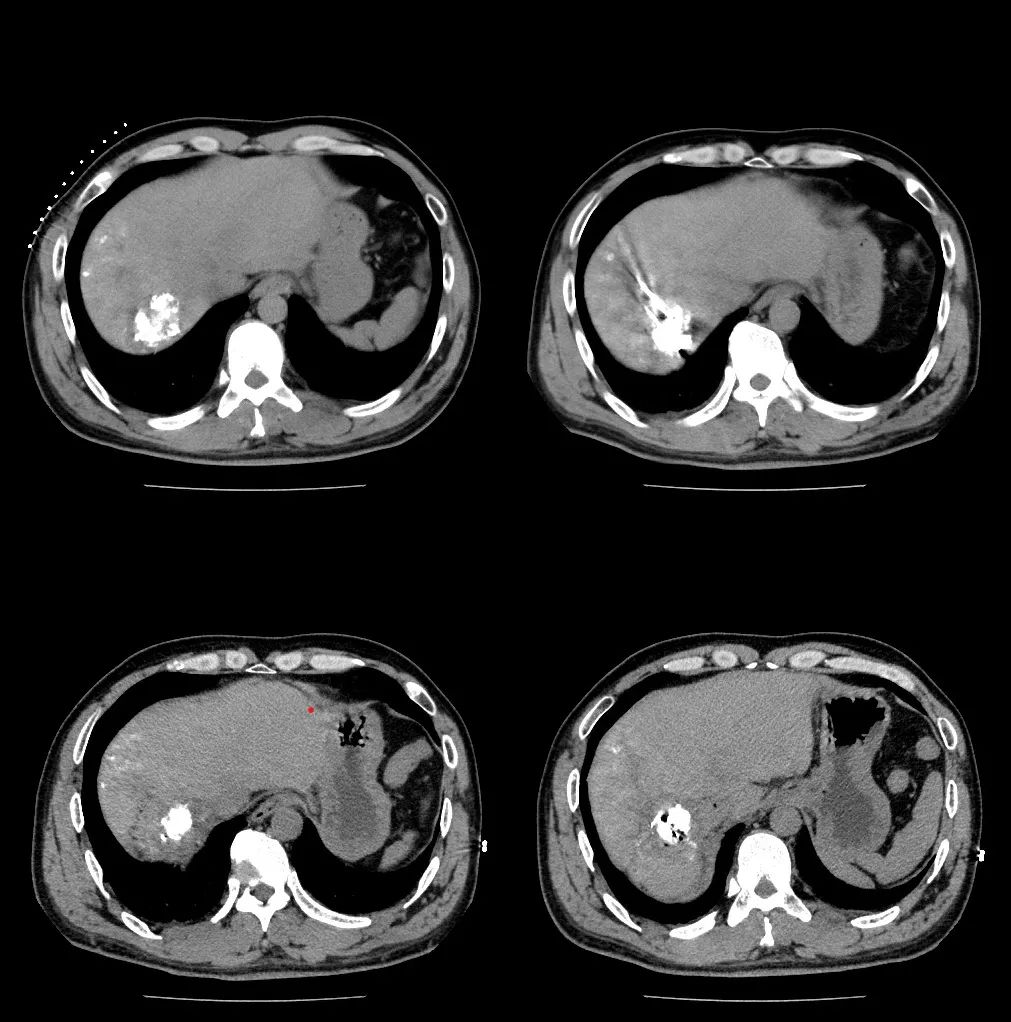

肝臟多期動(dòng)態(tài)MRI

結(jié)合患者的肝炎病史、甲胎蛋白升高及比較典型的肝癌影像學(xué)表現(xiàn),根據(jù)原發(fā)性肝癌診療指南(2022版)原發(fā)性肝癌診斷明確。

復(fù)查CT碘油填充肝癌病灶